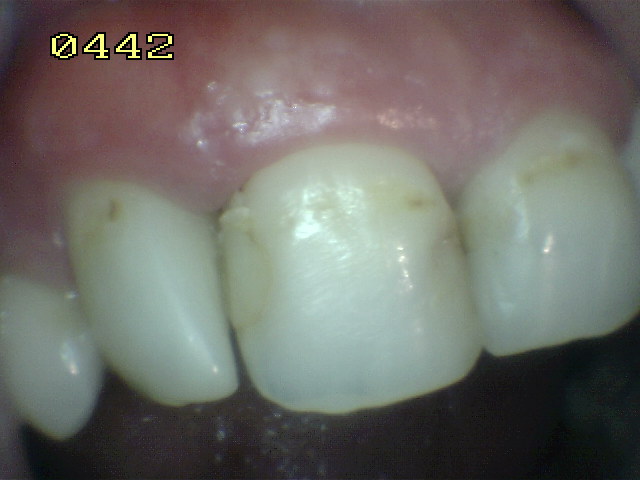

En 11 obturaciones de

clase 3 en mesial y distal con filtración marginal |